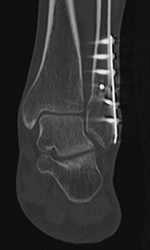

Fracture Union. (A) Sagittal multiplanar reformation demonstrates non-united distal fibular fracture. (B) Follow-up dual-energy CT coronal multiplanar reformation demonstrates distal fibular fracture healing after fixation for non-union.